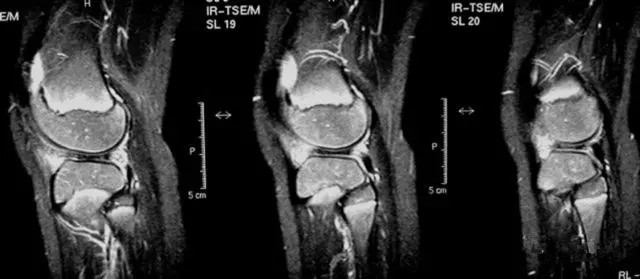

本书通过丰富的病例和大量精美的图片将现代成熟的诊断和治疗方法全面详实的呈现给读者,是一部系统的、专门阐述半月板外科技术的教科书。通过将笔者丰富的实践经验与读者分享,使更多从事运动医学和关节镜外科专业的骨科医师能进行完整的学习和系统提高。

本书围绕临床诊断和治疗进行了系统详细的介绍,突出其实用性:包括经典的自内向外和自外向内缝合技术、快捷易行的半月板固定物、精细的全内缝合钩缝合技术和半月板移植手术等,将"基础、经典和提高" 融于一体,对运动医学与关节镜专科医生、骨科住院医生和专科进修医生有非常大的帮助。

海量图片/先睹为快